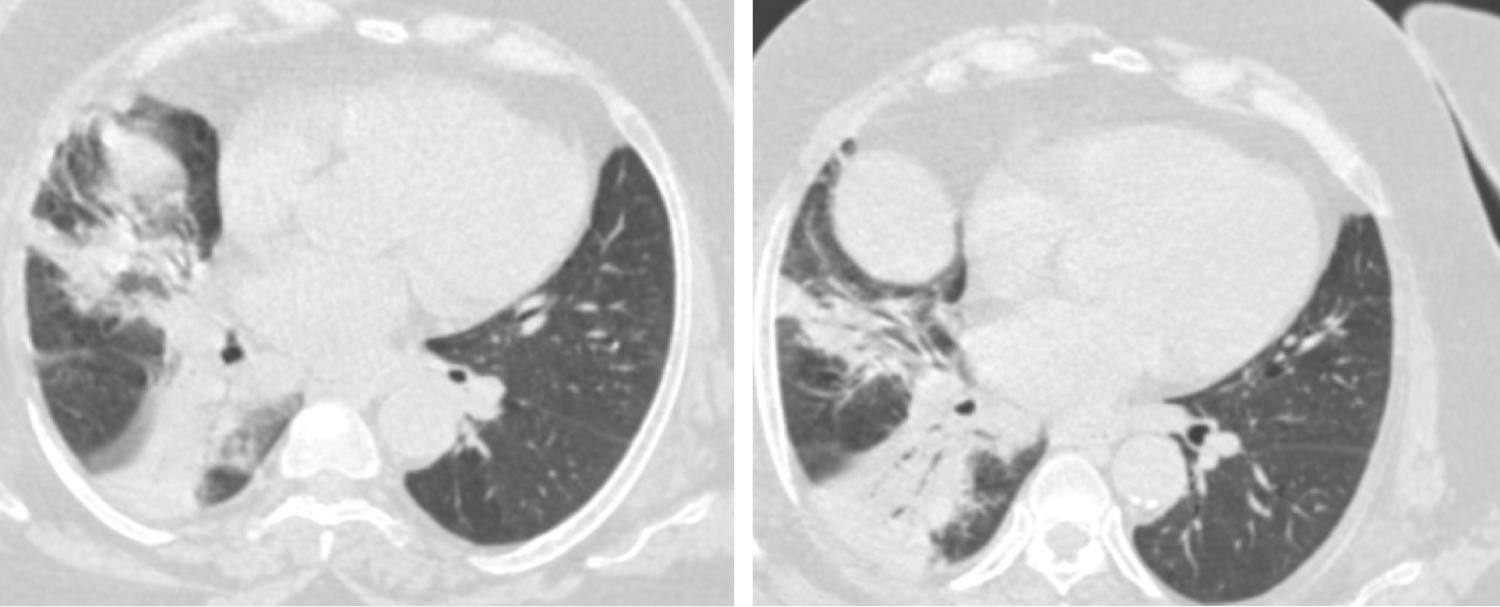

Figure 4: Female patient aged 37-years-old had negative initial reverse transcription-polymerase chain reaction results. Axial CT chest cuts shows bilateral ill-defined ground glass opacities with peripheral & sub-pleural in distribution seen at both upper and lower lung lobes these findings are highly suspected for COVID-19 (CORADS 4). View Figure 4

Figure 5: Male patient aged 60-years-old had positive initial reverse transcription-polymerase chain reaction results. Axial CT cuts show bilateral multi-focal ground glass opacities & smaller areas of consolidation are seen involving both lung fields with peripheral/subpleural predominance, this together with multiple subpleural lines this in keeping with viral pneumonia (COVID-19) (CORADS 5). View Figure 5